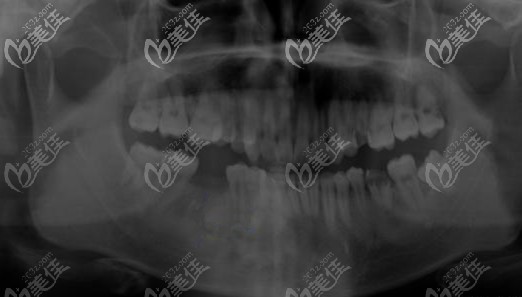

來院后,護(hù)士先帶我做了CBCT全景片,面診后醫(yī)生表示我的牙槽骨密度、高度都可以。

牙槽骨吸收為1度,但口內(nèi)的衛(wèi)生比較差,而且牙槽骨的高度、寬度都不錯(cuò),牙齦也沒有紅腫的情況。